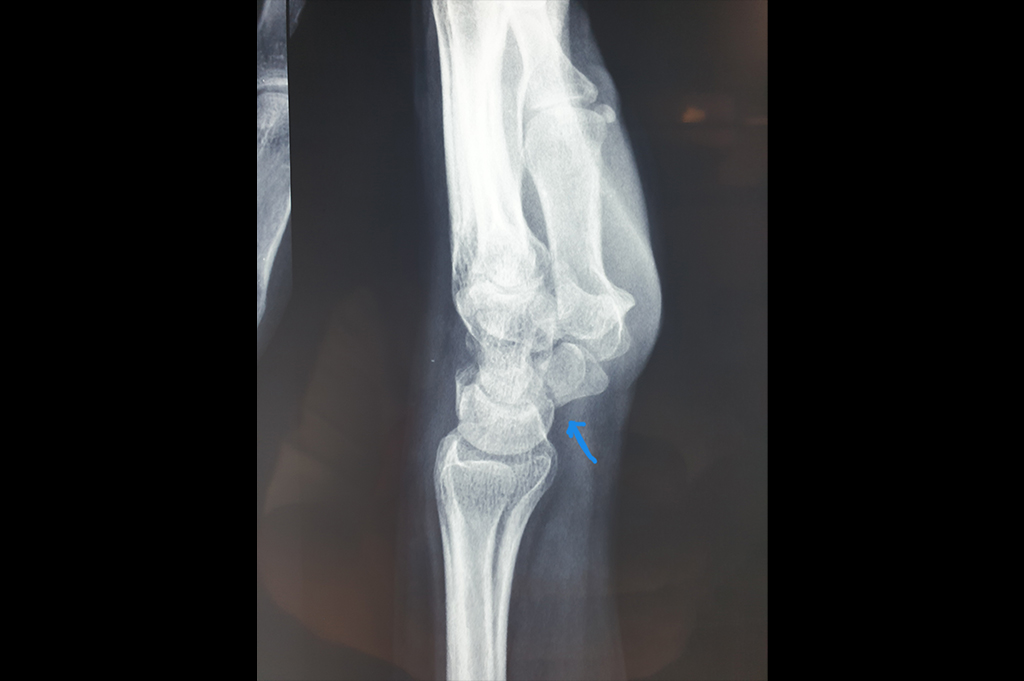

Elbow